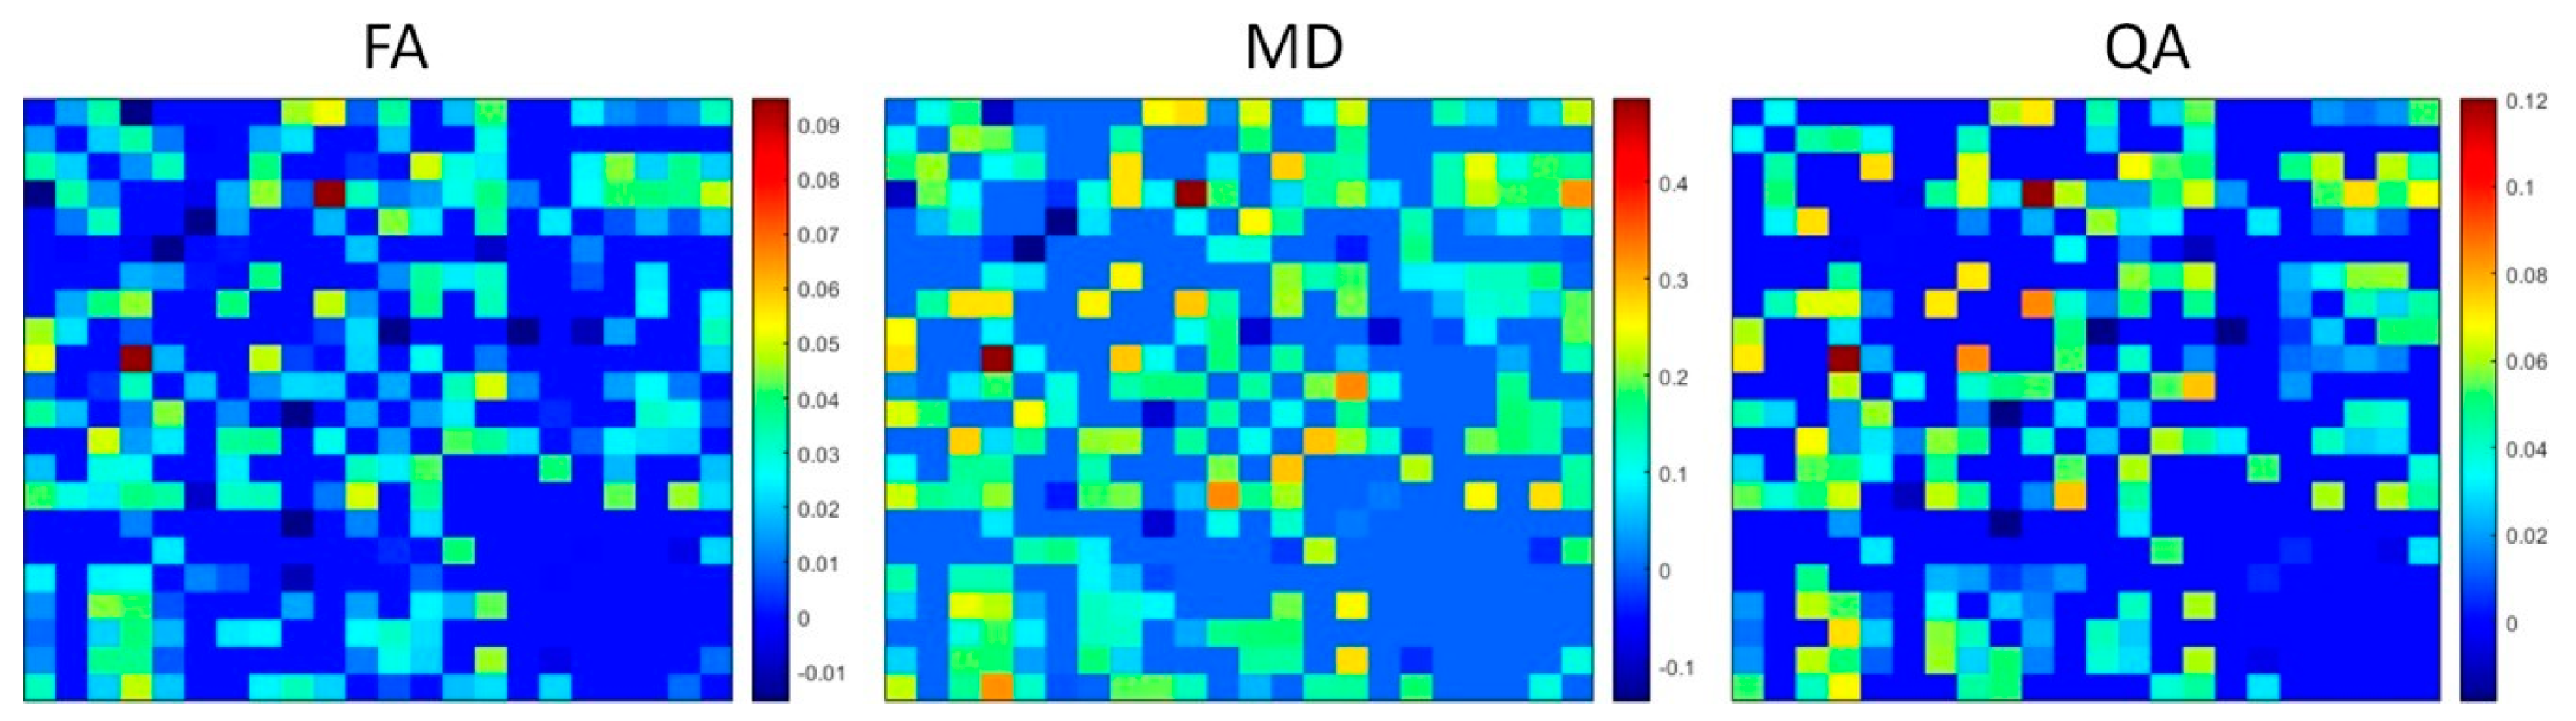

2.5. Statistical Analysis

3. Results